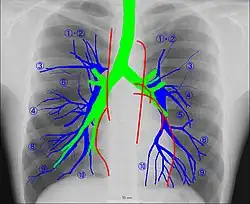

Human chest radiographic anatomy.

Radioanatomy (x-ray anatomy) is an anatomy discipline that involves studying anatomy through the use of radiographic films.[3] The x-ray film represents a two-dimensional image of a three-dimensional object due to the summary projection of different anatomical structures onto a planar surface.